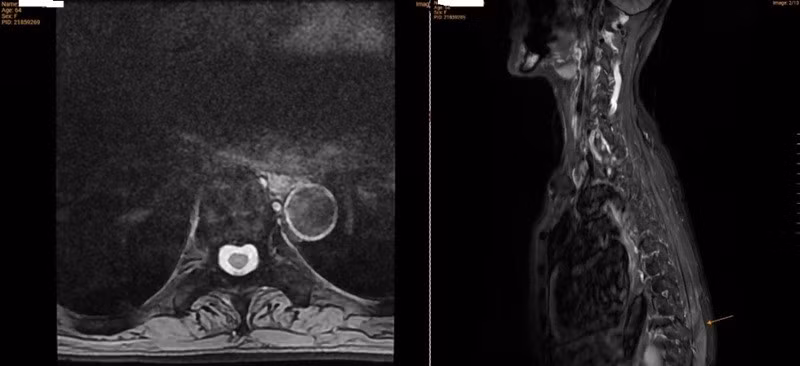

Kết quả chụp cộng hưởng từ (MRI) cột sống cho thấy, bệnh nhân có xẹp mới đốt sống L2 trên nền nhiều đốt sống xẹp mạn tính trước đó (T8, T10, T11, L4, L5), kèm theo tình trạng thoái hóa cột sống, phình và thoát vị đĩa đệm, cũng như viêm phần mềm vùng cột sống lưng – thắt lưng.

Kết quả chụp MRI của bệnh nhân ghi nhận nhiều đốt sống bị xẹp

Đo mật độ xương ghi nhận, mức độ loãng xương rất nặng, với T-score tại đốt sống L1–L4 là –3,4; cổ xương đùi phải –3,4 và cổ xương đùi trái –3,8.